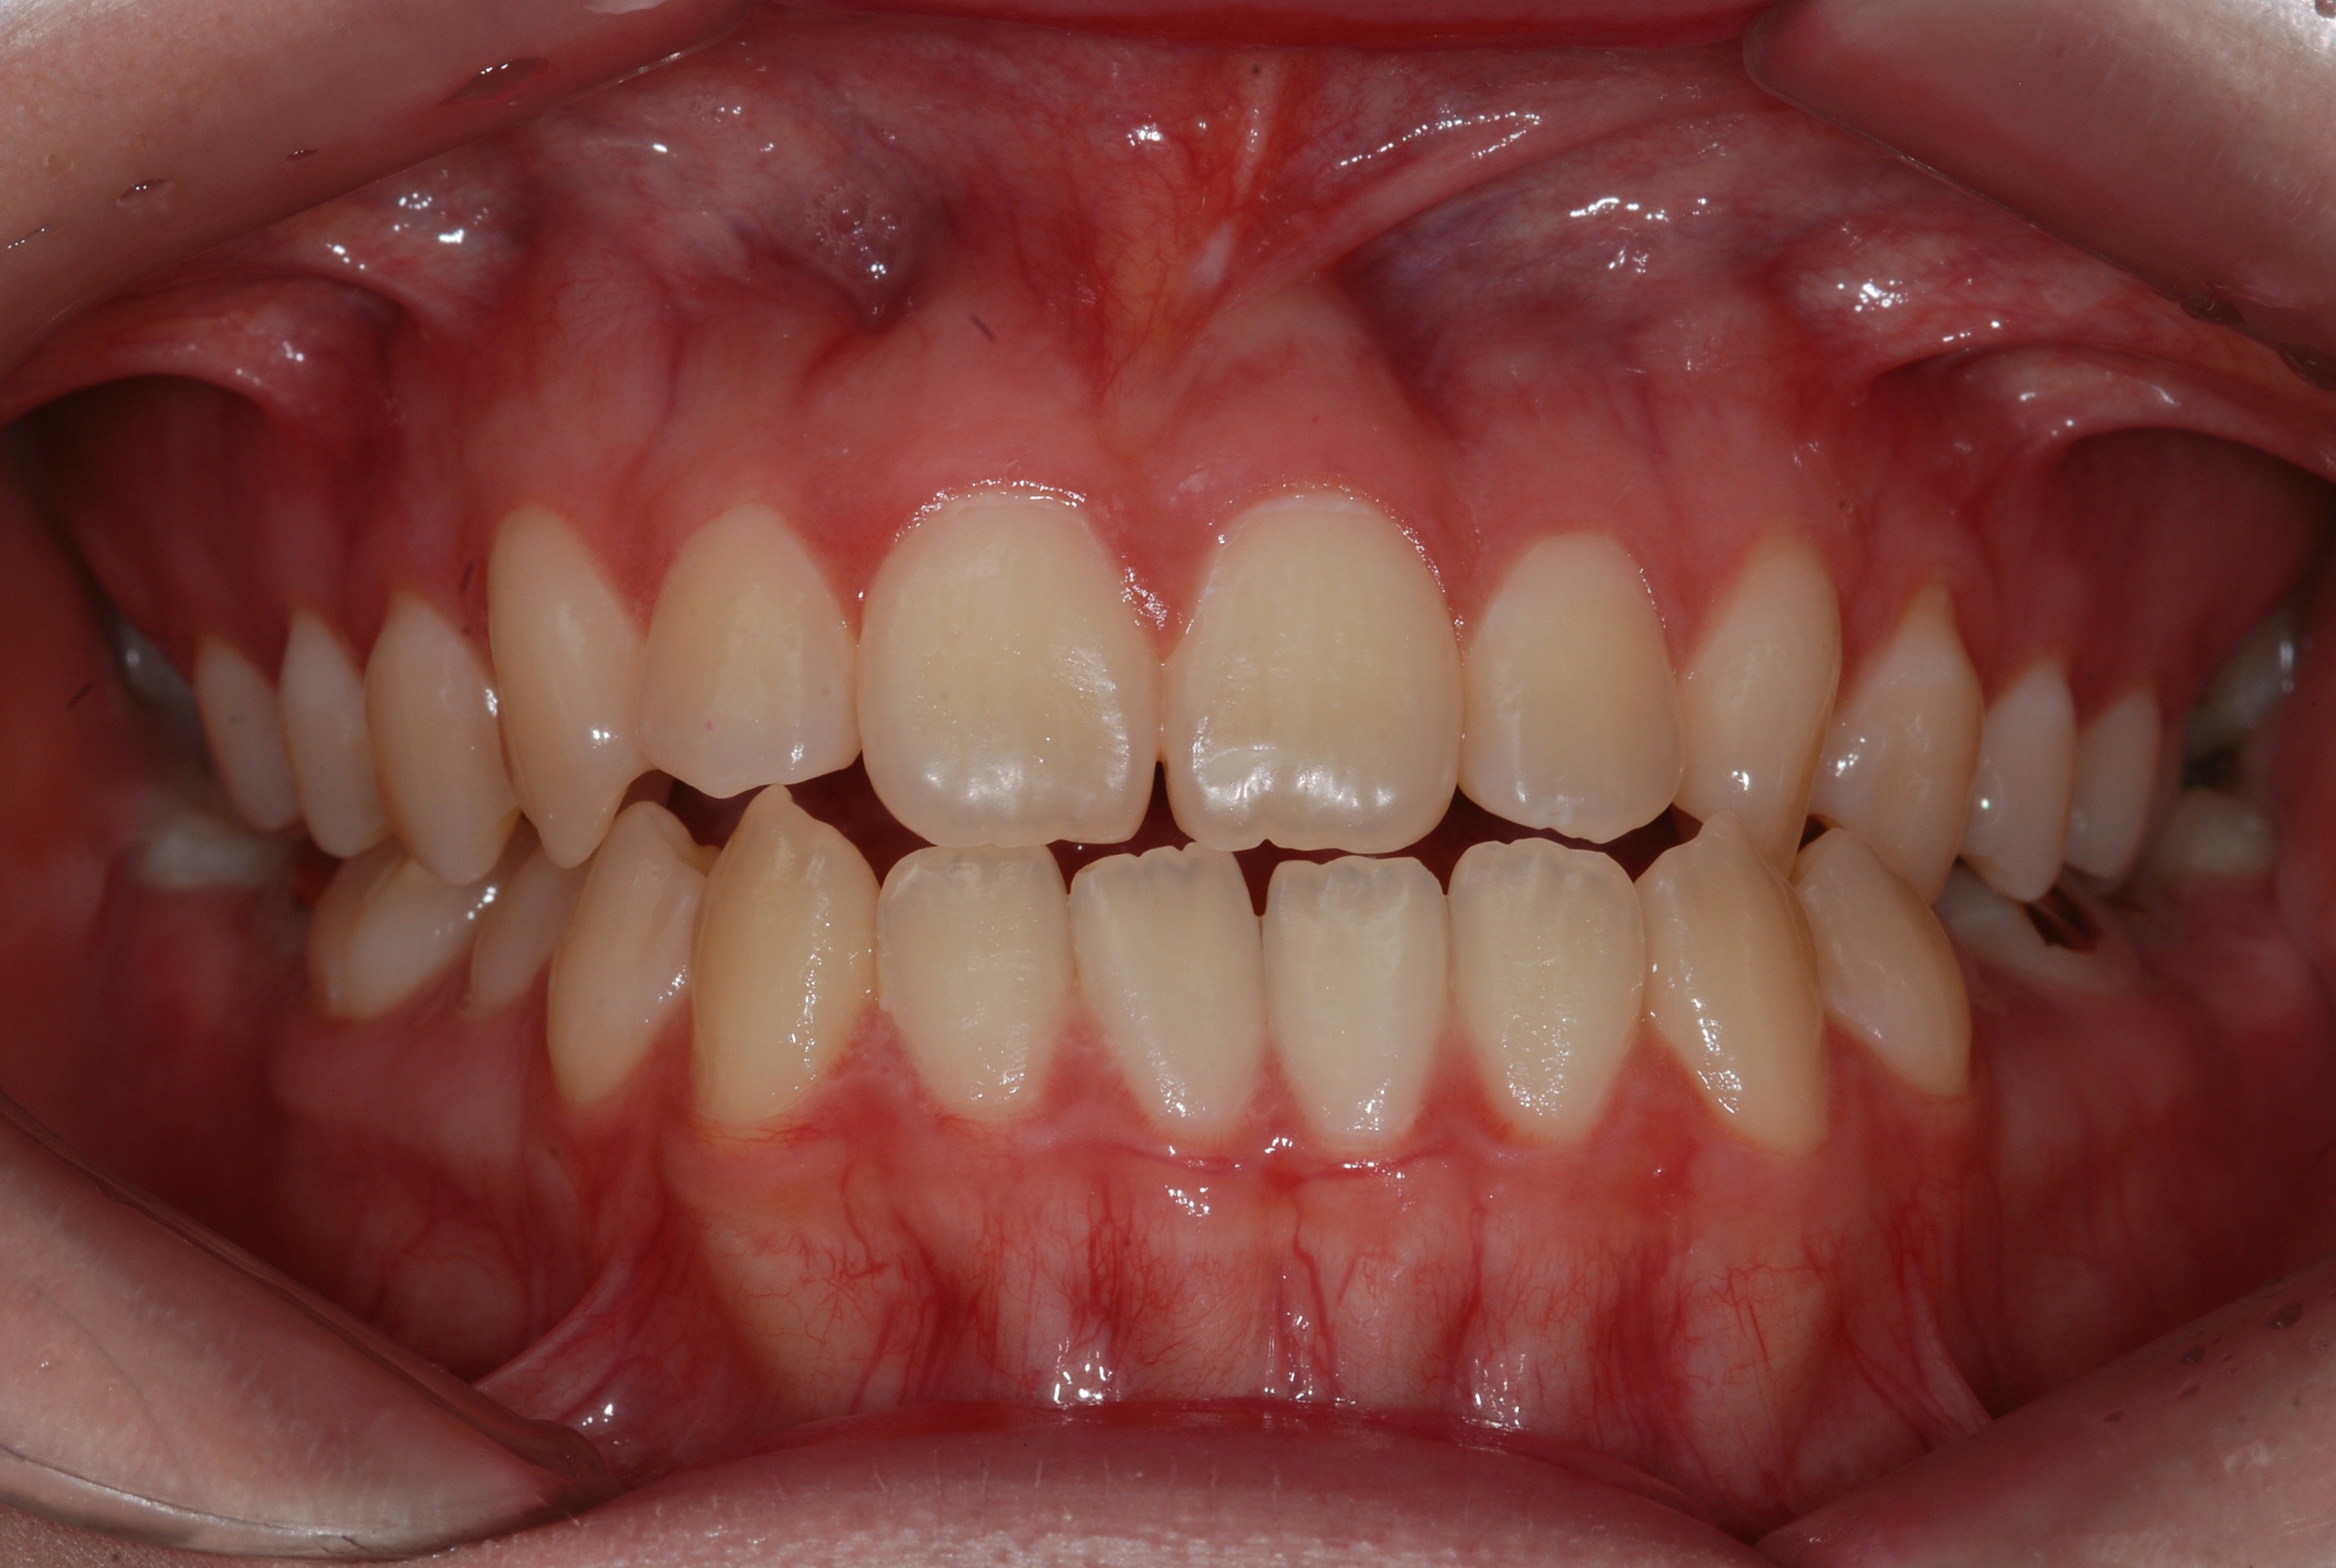

치료 후 사진입니다.